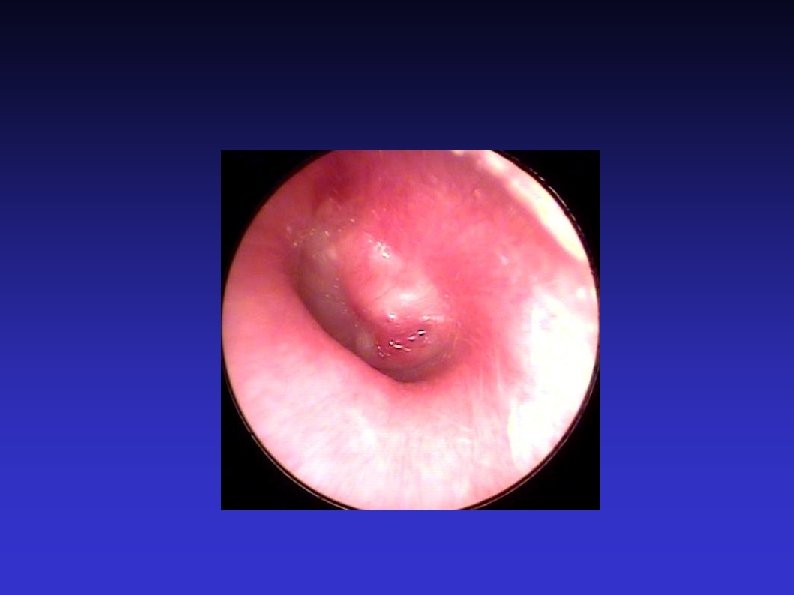

Examination of the nose 7) Post nasal space examination With mirror, Hopkins rod, or nasendoscope Not easy outside of ENT clinic Large masses, such as an antrochoanal polyp

Examination of the throat 5) Nasopharynx Unless large lesion, will need mirror, Hopkins rod or nasendoscope